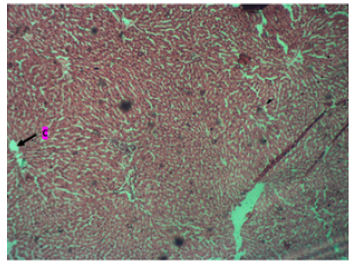

The histological result of the study in control animals, shows a portal triad (P) and central vein (C) with many surrounding hepatocytes with sinusoids. And the tissue appears normal as seen in (Plate 1).

Plate 1: Photomicrograph of the liver in the control group showing a portal triad (P) and central vein (C). There are many surrounding hepatocytes with sinusoids. Tissue appears normal. H & E. X200.

The liver's typical cellular and tissue architecture was demonstrated by the study's findings. The liver is made up of parenchymal cells, the portal triad (P), the central vein (C), and numerous other non-parenchymal cell types, all of which are important. In addition to being the target of autoimmune liver disorders, biliary epithelial cells also play a crucial role in the coordination of many immune cells involved in both innate and acquired immunity (Plate 1). Our current study's outcome is consistent with the conclusions of [9].

The study's histology findings for the control animals display a central vein (C) and portal triad (P) with many hepatocytes with sinusoids surrounding them. As can be seen in (Plate 1), the tissue looks normal. However, in the low dose group, the central vein (C) was visible, along with many surrounding hepatocytes with sinusoids, and the parenchyma displayed pseudorosettes tissue, as can be seen in (Plate 2) above. These results are consistent with research by Olagunju, et al. (2020) [18], which found that giving plantain weed extract reduced several markers of inflammation brought on by liver injury. On the other hand, the results of administering a high dose of aqueous extract from Musa Paradiasica reveal a central vein (C) surrounded by many hepatocytes with sinusoids. Additionally, as Plate 3 illustrates, the tissue looks normal. This finding is consistent with Redoy, et al.'s [18] research from 2021, which found that plantain weed extract significantly reduced inflammation and liver enzymes to prevent liver damage.